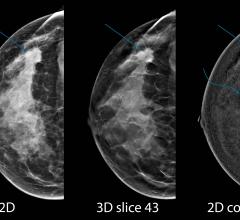

A machine learning tool can help identify which high-risk breast lesions are likely to become cancerous, according to a new study appearing online in the journal Radiology. Researchers said the technology has the potential to reduce unnecessary surgeries.

The Tomosynthesis Mammographic Imaging Screening Trial (TMIST), the first randomized trial to compare two types of digital mammography for breast cancer screening, is now open for enrollment. The study was developed by the ECOG-ACRIN Cancer Research Group (ECOG-ACRIN) and the National Cancer Institute (NCI), part of the National Institutes of Health. ECOG-ACRIN is leading the trial.